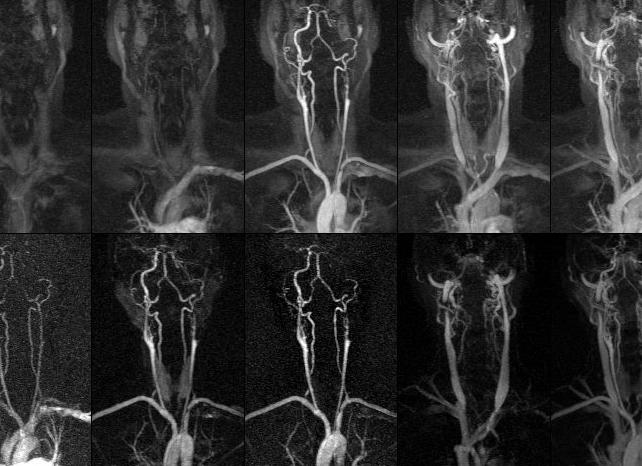

Томография чаще всего используется для сканирования и визуализации любых внутренних органов, в том числе головного и спинного мозга. Данный метод сканирования позволяет измерять скорость кровотока, показывать работу головного мозга и других внутренних органов, видеть диффузию в различных тканях. Процедура проводится от 20 до 40 минут.

Исследование проводится с помощью электромагнитных волн. Данный метод также считается безопасным. Однако электромагнитные волны реагируют на металлические предметы в организме человека, поэтому при наличии в голове несъемных металлических протезов получить достоверные показания невозможно, за исключением случаев, когда металл – амагнитный. МРТ противопоказана при беременности. Однако в отличие от УЗДГ, МРТ позволяет получить развернутое трехмерное изображение сосудов и выявить не только сосудистые проблемы, но также их причины и степень.

Сегодня стоит остро вопрос, а что лучше МРТ или УЗИ для исследования сосудов головного мозга и шеи. Как и в предыдущем случае томография дает самые точные результаты. Она позволяет выявить даже мельчайшие изменения и патологии, которые образовались в сосудах.

Чаще всего для исследования сосудистой системы головного мозга применяется томография с усилением. Она подразумевает под собой использование контрастирующего вещества, которое вводят пациенту внутривенно. Данный препарат зачастую изготавливают на основе солей гадония — они нетоксичны и полностью безопасны для здоровья.

При исследовании сосудов головного мозга и шеи также хорошие результаты дает ультразвуковая доплерография. Обследование осуществляется с помощью ультразвуковых волн, которые направляются непосредственно к сосудам. Благодаря методике доплерографии можно исследовать крупные сосуды.